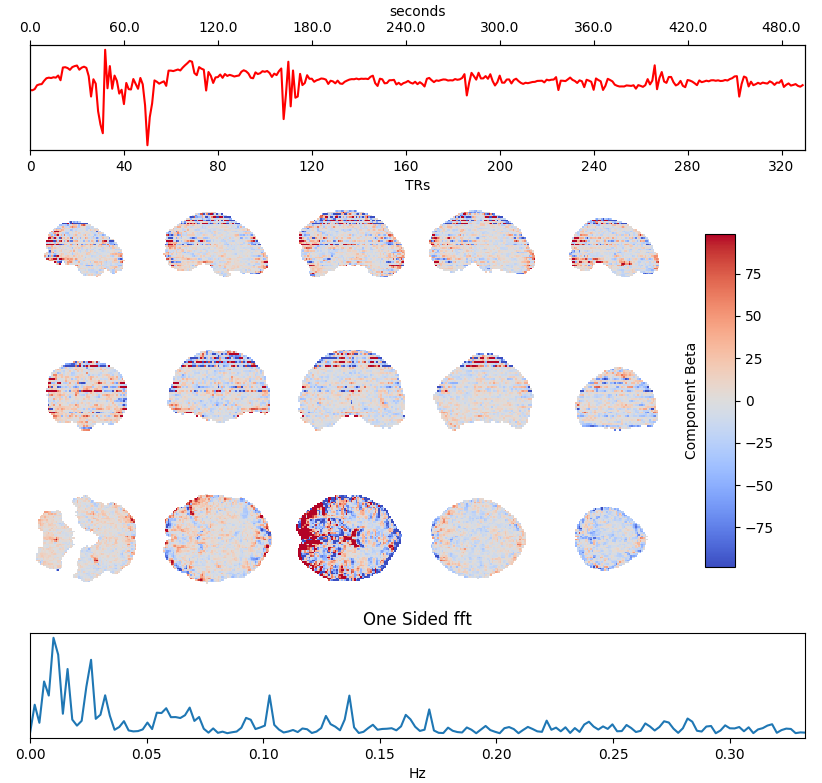

ICA denoising

Independent Component Analysis (ICA) is commonly used to remove motion effects and other sources of noise from fMRI data

Motion

Motion + MB artefact

CSF pulsations

Griffanti et al. 2014 (NeuroImage), 2017 (NeuroImage), The tedana Community et al. 2021 (Zenodo)

Which ICA denoising?

What is the best way to denoise BH data after ICA?

being too aggressive might remove the signal of interest,

but being too conservative might keep too much noise in the model.

Methods: ME-ICA based denoise

What is the best way to denoise BH data after ICA?

being too aggressive might remove the signal of interest,

but being too conservative might keep too much noise in the model.

- Aggressive model: nuisance regression using only noise ICA-components (ME-AGG): $$ Y_{OC} = P_{ET}CO_2{hrf} + Mot + Poly + [IC_{rej} \perp (Mot,Poly) ] + n $$

- Moderate model: noise components are orthogonalised w.r.t. the CO2 trace (ME-MOD): $$ Y_{OC} = P_{ET}CO_2{hrf} + Mot + Poly + [IC_{rej} \perp (P_{ET}CO_2{hrf},Mot,Poly) ] + n $$

- Conservative model: noise components are orthogonalised w.r.t. the CO2 trace and the other components (ME-CON): $$ Y_{OC} = P_{ET}CO_2{hrf} + Mot + Poly + [IC_{rej} \perp (P_{ET}CO_2{hrf},IC_{acc},Mot,Poly) ] + n $$

- Optimal combination only (OC-MPR): $$ Y_{OC} = P_{ET}CO_2{hrf} + Mot + Poly + n $$

- Single echo only (second echo used as proxy, SE-MPR): $$ Y_{SE} = P_{ET}CO_2{hrf} + Mot + Poly + n $$

We set up a simultaneous estimation and denoise step, considering motion parameters,

their derivative, Legendre polynomials to the fourth order, and:

- Aggressive model: nuisance regression using only noise ICA-components (ME-AGG): $$ Y_{OC} = P_{ET}CO_2{hrf} + Mot + Poly + [IC_{rej} \perp (Mot,Poly) ] + n $$

- Moderate model: noise components are orthogonalised w.r.t. the CO2 trace (ME-MOD): $$ Y_{OC} = P_{ET}CO_2{hrf} + Mot + Poly + [IC_{rej} \perp (P_{ET}CO_2{hrf},Mot,Poly) ] + n $$

- Conservative model: noise components are orthogonalised w.r.t. the CO2 trace and the other components (ME-CON): $$ Y_{OC} = P_{ET}CO_2{hrf} + Mot + Poly + [IC_{rej} \perp (P_{ET}CO_2{hrf},IC_{acc},Mot,Poly) ] + n $$

- Optimal combination only (OC-MPR): $$ Y_{OC} = P_{ET}CO_2{hrf} + Mot + Poly + n $$

- Single echo only (second echo used as proxy, SE-MPR): $$ Y_{SE} = P_{ET}CO_2{hrf} + Mot + Poly + n $$

Alternative ICA based denoise (sequential)

What is the best way to denoise the data after ICA?

Regression based:

Aggressive approach: nuisance regression using only the rejected components.

Non aggressive (partial regression) approach: all the components are considered, but only the rejected components are regressed out of the data.

Orthogonalised approach: the rejected components are orthogonalised with respect to the other components.

4D-based approach (similar to M/EEG): reconstruct volumes on noise, then subtract it from the original data.